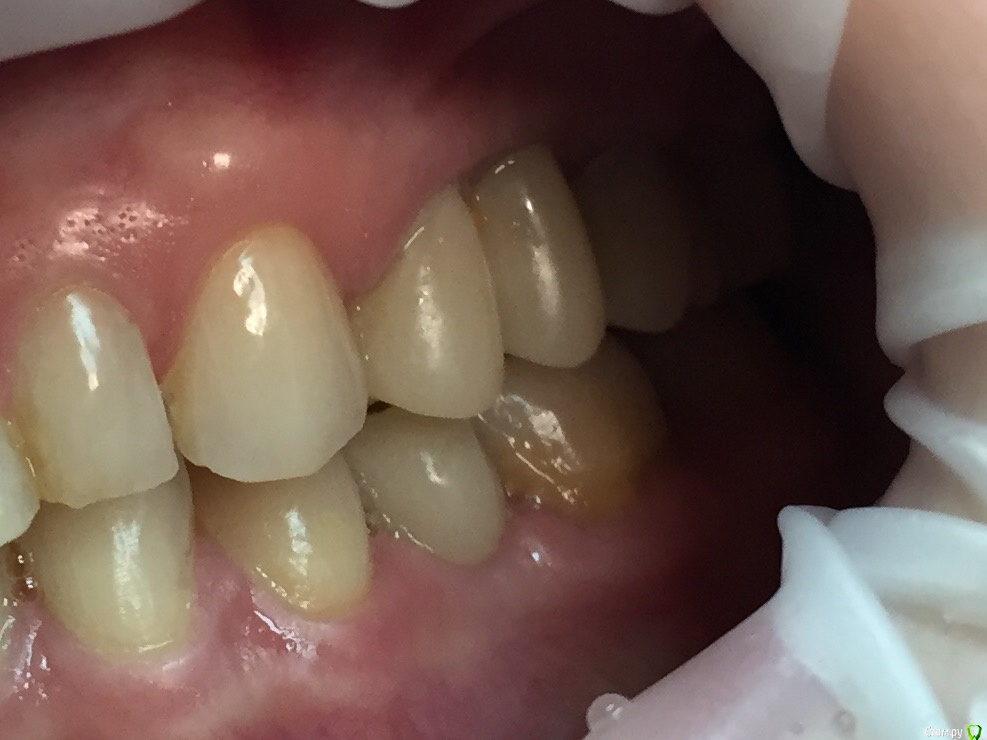

Глеб Митрофанов Опубликовано 12 сентября, 2015 Поделиться Опубликовано 12 сентября, 2015 (изменено) Направлена ортопедом , к которому пришла от другого хирурга и ортопеда , которые оперировали и изготавливали времянки соответственно . Пришла с просьбой - хочу сосочки ! Изменено 12 сентября, 2015 пользователем Глеб Митрофанов Ссылка на комментарий

Глеб Митрофанов Опубликовано 12 сентября, 2015 Автор Поделиться Опубликовано 12 сентября, 2015 А какой вопрос? С какой целью написали?Что возможно сделать , чтоб сделать максимально приближенное к желаемому ? Работа с мягкими тканями , времянками ?? Ссылка на комментарий

faity Опубликовано 12 сентября, 2015 Поделиться Опубликовано 12 сентября, 2015 пластика с бугров наверху, снизу полностью переделывать ортопедию и делать пластику с бугров. Гамборена вчера показывал как))) carlos показывает уже год 4 Ссылка на комментарий

Aquarius Опубликовано 12 сентября, 2015 Поделиться Опубликовано 12 сентября, 2015 Что возможно сделать , чтоб сделать максимально приближенное к желаемому ? Работа с мягкими тканями , времянками ??Если имплант не глушить, то по моему никак Ссылка на комментарий

Mane Опубликовано 12 сентября, 2015 Поделиться Опубликовано 12 сентября, 2015 снимаешь временную коронкупересаживаешь сст с бугра на тонкий формировательждешь месяцоцениваешьпротезируешь 2 Ссылка на комментарий